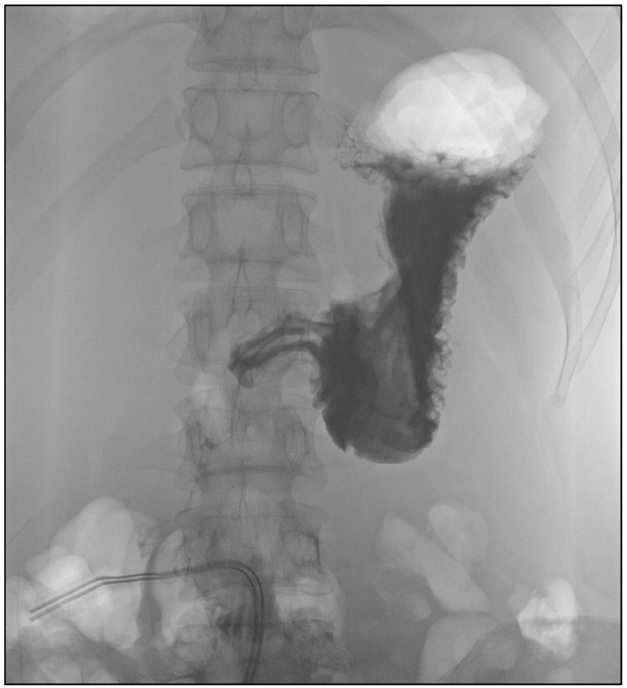

Figure 2: Postoperative imaging of the gastro-intestinal passage Postoperatively, we performed an X-ray series of the stomach upon application of contrast medium. This revealed a re-tonised, normal-sized stomach without evidence for stenosis.

A 28-year-old woman presented in our surgical emergency unit with a sudden onset of progressive abdominal discomfort and pain. Anamnestically, the patient denied any preexisting conditions or previously performed surgeries. The patient was not under any long-term medication. Physical examination revealed a distended and meteoritic abdomen with signs of peritonism. Routine laboratory analysis did not show any pathologies, including normal hemoglobin, leucocytes, C-reactive protein (CRP) as well as serum electrolytes. Because of the acute and dramatic clinical presentation we immediately performed a computed tomography of the abdomen. This revealed a massively distended stomach with a cranio-caudal extension of 35 cm reaching the lesser pelvis, however, without evidence for perforation (Figure 1 [Fig. 1]). Initially, the cause for the distention remained elusive. The patients was admitted to our intensive care unit. A stomach tube was placed, which, however, did not drain any significant amount of stomach content. We therefore decided on an emergency explorative laparotomy on the same day. Intraoperatively, in addition to the massively dilatated stomach no abnormalities were detected. We performed a gastrotomy of the gastric antrum and recovered (over the period of one hour) a large amount of cementitiously clotted and undigested food scraps from the stomach. Subsequently, the stomach was closed by sutures and an intraabdominal drainage was placed. An intraoperative performed gastroscopy did not reveal any stenosis or other pathologies. The postoperative course was without complication. The stomach tube as well as the intrabdominal drainage could be removed within the first days after surgery. A gradual reintroduction of liquids was well tolerated. On the sixth postoperative day we performed a radiological imaging of the stomach using contrast medium which revealed a re-tonised stomach of a normal size without evidence for any stenosis (Figure 2 [Fig. 2]). Subsequently, the patient was allowed to normal food intake, which was well tolerated as well. The postoperatively initiated evaluation of the patient by a psychiatrist revealed that she had been suffering from an eating disorder since her childhood. This was initially characterized by an anorectic behavior with starvation und excessive exercising. Temporarily, her body mass index (BMI) had dropped to 11 kg/m². At consultation in our clinic her BMI was in the lower normal range. However, the patient reported on daily binge eatings caused by conflicts at her workplace. This had also occurred on the day of hospital admission, however on this day, the routinely self-induced vomiting after the binge attack failed. In a good status of health the patient could be dismissed from our clinic on the 13th postoperative day. The psychiatric co-treatment therapy was continued.